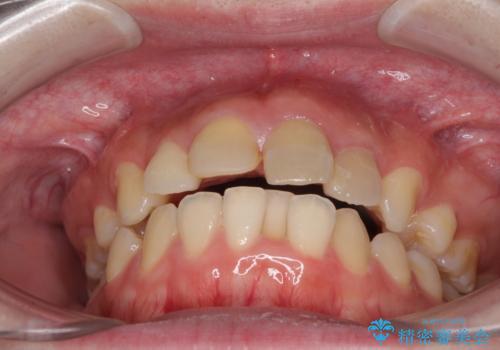

抜歯矯正の後戻り インビザラインによるオープンバイトの再矯正

- 以前矯正治療をされていましたが、後戻りが起きたことを気にして来院された患者様です。

上下前歯のオープンバイトを改善するため、インビザラインにて治療を行うこととしました。

外食が楽しみである患者様だったので、インビザラインによる治療期間は我慢の時期であったようです。

自己管理を徹底していただいたので、1年程度で治療を終えることができました。